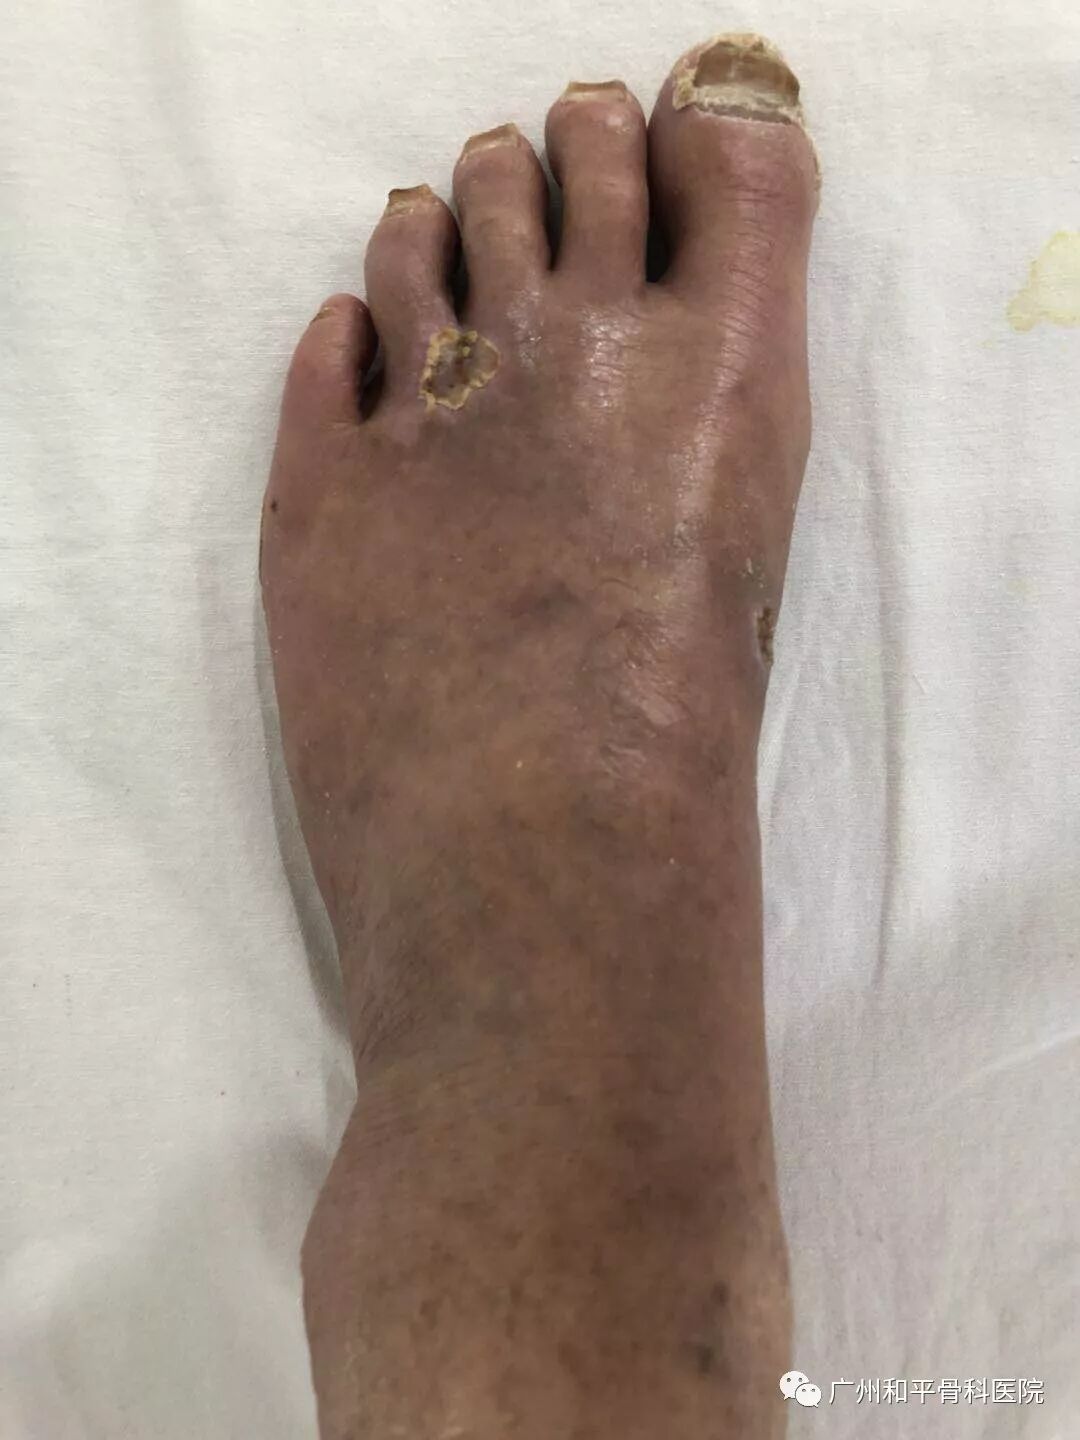

和平资讯 2019年04月19日 酷热的夏季袭来,对于长期卧床或者身有创面的人来说,更是难熬。广州和平骨科医院在显微外科技术修复创面的基础上,增加了抗生素骨水泥填塞覆盖、组织再生、胫骨横向骨搬运等技术,给不少慢创患者解决了难题。 慢性难愈性创面,通常可以理解为在各种内在或外界因素作用下创面不能通过正常的创面愈合进程达到愈合,进入一种病理性炎症反应状态,从而导致创面经久难愈。普遍可见的病症有糖尿病足、褥疮、下肢血管性疾病引起的慢性溃疡创面。 (糖尿病足) 广州和平骨科医院手外四科主任兰荣玉介绍,慢性难愈性创面是外科中长期难以解决的治疗难题,造成了患者较高的致残率。现有的一些治疗措施是基于普通创面模型,而非难愈创面,相关的一些基础研究也主要集中在国外,国内的研究在临床层面的较多,普遍应用显微外科技术如皮瓣移植来修复创面。“我们在此基础上增加了抗生素骨水泥填塞覆盖、组织再生、胫骨横向骨搬运等技术,丰富了治疗方法和手段,让不同程度的慢创患者受益。”兰荣玉介绍。 (皮瓣移植过程) 59岁的李强(化名)此前为自己的创面痛苦不已。他的左足背多处溃疡创面、组织糜烂,异常分泌物,足背及外踝广泛皮肤可见明显红肿,针尖大小疱疹生成伴轻度瘙痒,如果继续恶化可能需要截肢。广州和平骨科医院创伤显微手外四科医生为他进行慢性创面治疗,采取微创治疗,期间采用组织再生及创面湿润愈合技术,去腐生肌,李强左足保肢完全成功并完全康复,无需手术治疗。 52岁张翠(化名)与李强一样也是老病号,因长期卧床导致了自己右臀部溃疡及分泌物渗出严重,更让她难受的是她出现了左臀部瘢痕痉挛、慢性创面溃疡,双下肢瘫痪,兰荣玉主任为她开展了手术治疗术后,她的创面愈合较好,让她了了一桩难事。 慢创修复-G4出动20190418_广州广播电视台 广州和平骨科医院(原广州和平手外科医院)是一家拥有二十多年历史的国家二级非营利性医院,是以手足显微外科、四肢创伤及脊柱关节科为主要学科的骨科医院,是华南地区创建早、规模大、技术力量雄厚、设备先进的医院。 广州和平骨科医院(原广州和平手外科医院)经广州市卫计委批准成立,是广州市医保、广州市工伤保险、东莞市工伤保险及PICC等保险公司定点医疗机构;是广州市医疗工伤生育保险研究会常务理事单位。 医院可开设床位300张。重点科室有:创伤显微手外科中心、创伤骨科中心、 脊柱关节骨科中心、康复医学中心、慢创治疗中心等多个重点专科和多个精细亚专科。 医院配备先进的百级层流手术室、先进的麻醉呼吸机、德国西门子螺旋CT、DR、C型臂X光机、高频专用摄像系统、彩超、多功能监护仪、大型全自动检验设备、高倍手术显微镜、阿基米德运动康复系统、多功能神经康复治疗仪等多种大型先进设备。 医院主要开展四肢脊柱关节创伤、断指(肢)再植、手指缺损再造、四肢血管神经肌腱修复、大面积组织缺损的皮瓣修复、四肢先天畸形矫正等。断指再植和手指再造成功率达国内领先水平。尤其擅长婴幼儿断指、十指多平面离断等复杂严重及罕见病例的修复。并且开展各类专业的中西康复理疗。 我院始终坚持优质服务与精湛技术相结合,收治一位患者,减少一份残疾;推广真技术,传递正能量。 我们的理念是:患者至上,良医为本,至精至善,共创共赢。 和平网站 www.hpswk.com 长按识别码关注我们 邮箱:2465389714@qq.com 电话:020-89636593 地址:广州市海珠区聚德南路112-120(双号)慢性难愈性创面修复

慢创病例